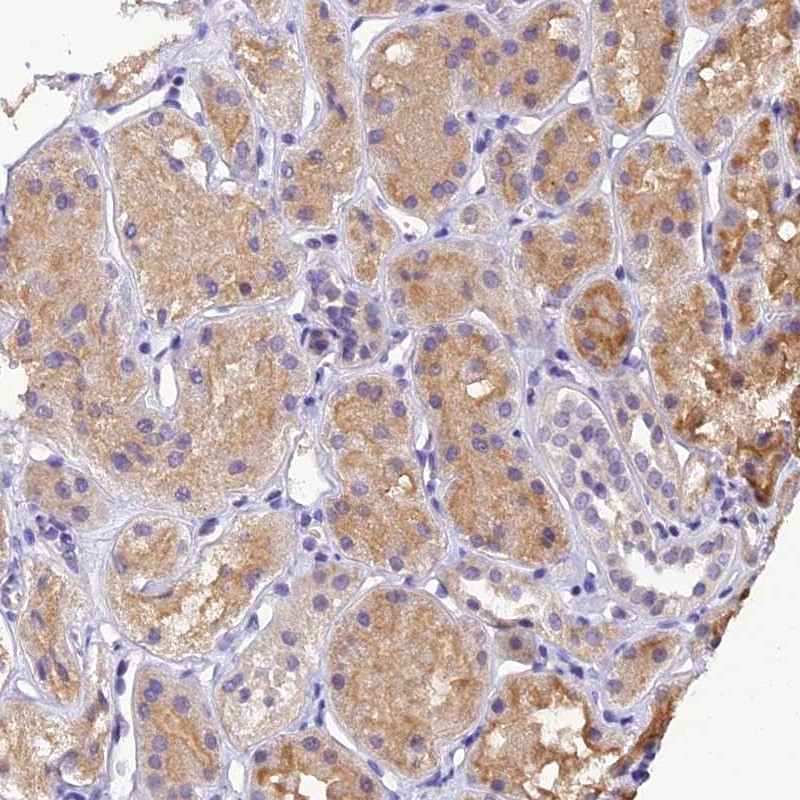

Immunohistochemical staining of human kidney shows moderate cytoplasmic positivity in renal tubules.